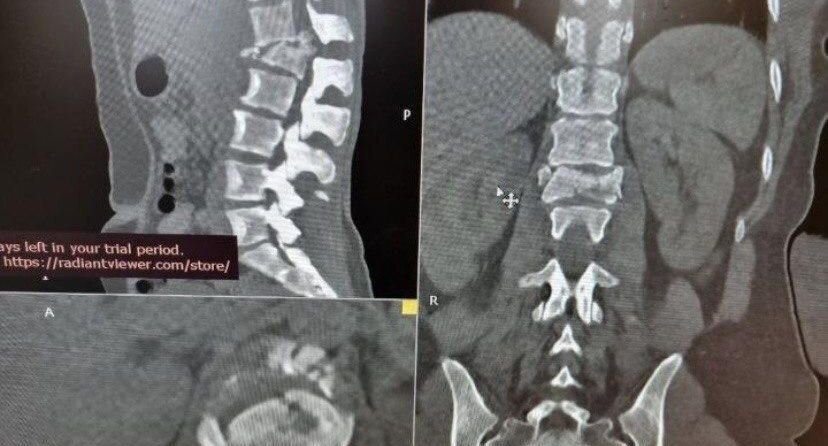

Женщина 34 лет поступила в больницу Долгопрудного с оскольчатым переломом поясничного позвонка. Во время курения она упала с балкона пятого этажа. Травма вызвала нарушения движения ног и работы органов таза. Врач-нейрохирург Павел Савинков рассказал, что пациентке провели сложную операцию — ей удалили отломки позвонка, сдавливающие спинной мозг. «Сломанный позвонок полностью замещен титановым протезом», — рассказал он. Двигательные функции после операции восстановились, женщину скоро выпишут из больницы. Ранее губернатор Андрей Воробьев анонсировал дополнительные премии медработникам в Подмосковье. Их получат фельдшеры, средний медицинский персонал, а также медики узких специальностей.

Женщина 34 лет поступила в больницу Долгопрудного с оскольчатым переломом поясничного позвонка. Во время курения она упала с балкона пятого этажа. Травма вызвала нарушения движения ног и работы органов таза.

Врач-нейрохирург Павел Савинков рассказал, что пациентке провели сложную операцию — ей удалили отломки позвонка, сдавливающие спинной мозг.

«Сломанный позвонок полностью замещен титановым протезом», — рассказал он.

Двигательные функции после операции восстановились, женщину скоро выпишут из больницы.